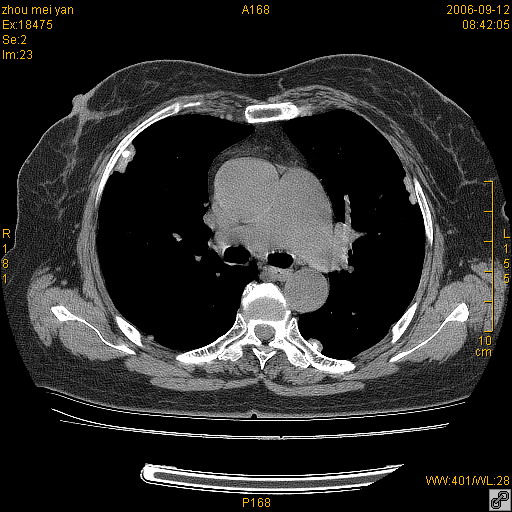

患者、女、55岁。因心率失常住院检查ct发现胸部多发结节。腹部b超肝、胆、胰、脾、肾、子宫附件未见异常。无结核病史,无粉尘接触史。请大家来会诊。谢谢!

病变位于胸膜,多发结节,边界清楚,内见小结节状钙化。其它未见异常。

双侧胸膜多发结节,形态不规则,边缘较清楚,每一个结节中心似乎都有钙化点的特征,与胸膜广基相切。临床无结核病史,无粉尘接触史。

胸膜间皮瘤可能性大。在气管隆突前可见一肿大淋巴结影。

影像表现十分有特点:双侧肋胸膜及膈胸膜广泛散在分布大小在2至6mm左右,较大病灶中心可见钙化。

考虑恶性胸膜间皮瘤可能性大,病灶位于胸膜,以宽基地与胸膜相连,呈结节样改变,部分病灶内可见点状钙化影。请各位老师多多指导!

双侧肋胸膜及膈胸膜广泛散在分布大小不等结节影,较大病灶中心可见钙化。